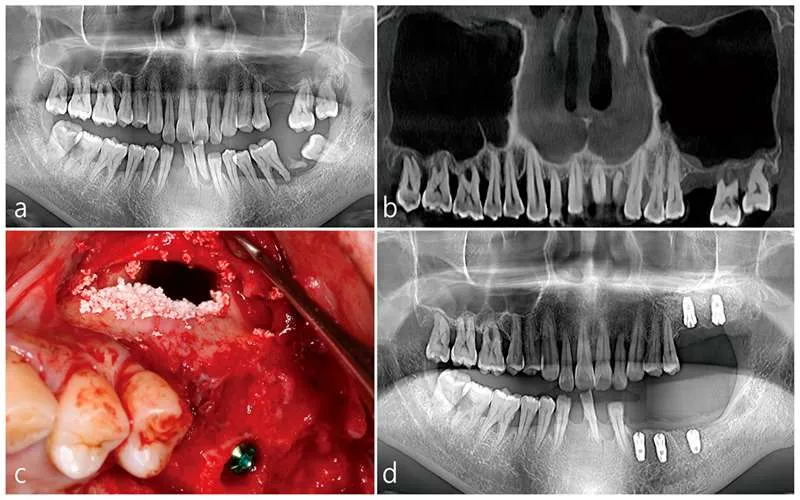

اگر تراکم استخوان به اندازه کافی نباشد، احتمال شکست پروسه کاشت ایمپلنت وجود دارد. به عبارتی عمل لیفت سینوس بسته با توجه به میزان آتروفی استخوان و موقعیت بافت استخوانی انجام می شود.

جراحی سینوس لیفت برای ایمپلنت به صورت بسته با هدف بالا بردن سینوس ماگزیلاری و پر کردن شکاف با مواد لازم پیوند استخوان انجام می شود. این پروسه به تشکیل بافت استخوانی کمک زیادی می کند.

هنگامی که استخوان دندان حجم خود را از دست می دهد، کاشت ایمپلنت امکان پذیر نیست. اگر بافت استخوانی دارای فضای کافی نباشد، امکان شکست پروسه ایمپلنت نیز وجود دارد. به همین منظور، عمل سینوس لیفت بسته باید قبل از کاشت دندان انجام شود.

- انجام معاینات و تصویربرداری دقیق قبل از عمل